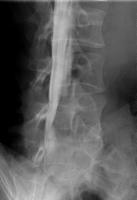

ミエログラフィー

背中に針を刺して、神経が通っている硬膜管内に造影剤を注入し、脊柱管の形状や障害を調べる検査です。

姿勢を変えたときの脊柱管の変化も見ることができるので、手術による治療計画を立てる際に役に立ちます。

ミエログラフィー後にCT検査を追加することで、より詳細に脊柱管の状態を見ることができます。